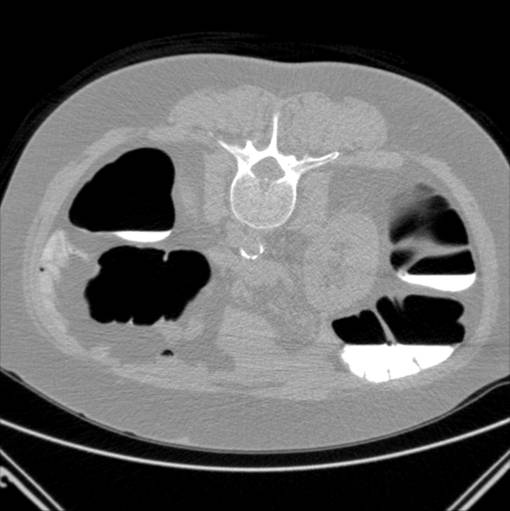

CT skanning af abdomen med henblik på fremstilling af tyktarmen (colon). Et af mange billeder. Patienten ligger på ryggen.